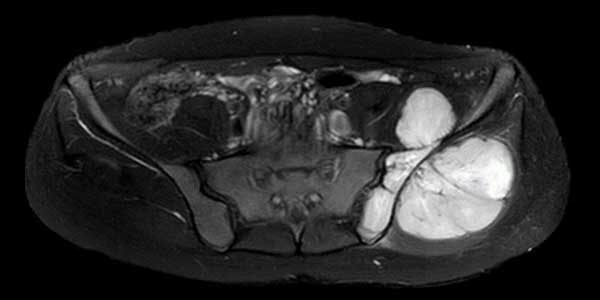

It is also called aggressive fibromatosis. The exact cause is unknown, but in some cases it has been associated with estrogen and trauma. Genetic background (familial adenomatous polyposis, Gardner syndrome) may be associated. Patients should be screened for this (family history of colon cancer) and colonoscopy should be performed in appropriate cases.

It is a benign but locally aggressive tumor. In other words, it can cause bone and joint destruction in the area where it is located and has a high risk of recurrence after surgery.